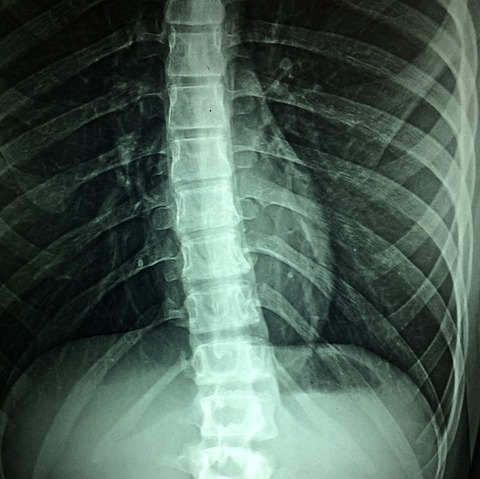

경피적 척추 성형술(Percutaneous vertebroplasty)은 척추 골절, 특히 골다공증으로 인한 골절을 치료하기 위해 고안된 최소 침습적 시술입니다. 이 시술은 골절된 척추에 뼈 시멘트를 주입하여 뼈를 안정시키고 통증을 완화하는 것을 포함합니다. 신속한 완화와 이동성 향상을 제공하는 기능을 갖춘 경피적 척추 성형술은 척추 압박 골절로 인해 심한 요통을 겪는 환자들에게 인기 있는 치료 방법이 되었습니다. 이 글에서는 경피적 척추 성형술(Percutaneous vertebroplasty)의 정의, 이점 그리고 적응증 대해 살펴보겠습니다.

경피적 척추 성형술(Percutaneous vertebroplasty)은 특수 바늘을 피부를 통해 영향을 받은 척추에 삽입하는 시술입니다. 일단 자세를 취하면 뼈 시멘트 혼합물을 척추에 주입하여 척추를 안정시키고 추가 골절의 위험을 줄입니다. 시멘트는 빠르게 굳어져 골절된 뼈를 지지하고 척추의 안정성을 회복시켜 즉각적인 통증 완화를 제공합니다. 이 시술은 일반적으로 환자가 깨어 있는 상태에서 국소 마취 하에 진행되지만, 진정제는 편안함을 위해 사용할 수도 있습니다. 이 시술은 주로 골다공증 환자에게 흔한 척추 압박 골절을 치료하는 데 사용됩니다. 압박 골절은 척추가 약화되고 붕괴되어 통증, 키 손실, 잠재적인 신경 압박으로 이어질 때 발생합니다. 경피적 척추 성형술(Percutaneous vertebroplasty)은 척추의 추가 손상을 예방하고 기능을 회복하는 데 도움이 됩니다.

경피적 척추 성형술(Percutaneous vertebroplasty)의 가장 흔한 적응증 중 하나는 골다공증으로 인한 척추 압박 골절입니다. 골다공증은 뼈가 약해지고 부서지기 쉬워져 특히 척추에서 골절이 발생하기 쉬운 질환입니다. 이러한 골절은 심한 요통, 키 손실, 이동성 저하로 이어질 수 있습니다. 진통제나 물리치료와 같은 보존적 치료가 충분한 완화를 제공하지 못하는 경우 경피적 척추 성형술(Percutaneous vertebroplasty)을 권장할 수 있습니다. 골절된 척추에 뼈 시멘트를 주입하여 뼈를 안정시키고 추가 붕괴를 방지하며 장기적인 통증 완화를 제공합니다. 특히 골절로 인해 상당한 통증을 경험하고 다른 치료에 반응하지 않는 환자에게 효과적입니다. 경피적 척추 성형술의 또 다른 중요한 적응증은 전이성 암으로 인한 척추 골절입니다. 척추로 전이되는 암은 척추를 약화시켜 골절에 더 취약하게 만들 수 있습니다. 이러한 골절은 치료하지 않으면 쇠약해지는 통증, 신경 압박, 심지어 마비를 유발할 수 있습니다. 경피적 척추 성형술은 골절된 척추를 안정시키고 통증을 완화하는 데 도움이 될 수 있으며, 이는 화학 요법이나 방사선 치료와 같은 다른 치료를 받고 있는 암 환자에게 특히 중요합니다. 척추 성형술은 통증 완화와 구조적 지원을 제공함으로써 척추 전이 환자의 삶의 질을 향상해 치료 기간 동안 더 활발하고 편안하게 지낼 수 있도록 합니다. 일부 경우에는 외상이나 부상으로 인해 척추 골절을 입은 환자에게 경피적 척추 성형술이 적용됩니다. 여기에는 사고, 낙상 또는 척추에 직접적인 충격이 가해져 골절이 발생할 수 있습니다. 외상 관련 골절은 골다공증으로 인한 골절보다 흔하지는 않지만, 골절이 아프고 다른 치료법이 적절한 완화를 제공하지 않는 경우에도 척추 성형술의 혜택을 받을 수 있습니다. 외상으로 인한 골절이 심각한 통증이나 기능 장애로 이어질 경우 경피적 척추 성형술(Percutaneous vertebroplasty)은 손상된 척추를 안정시키고 신경 손상과 같은 추가 합병증을 예방하는 데 도움이 될 수 있습니다. 이 시술은 더 빠른 통증 완화와 환자의 이동성 회복을 도와 부상으로 인한 장기 장애 위험을 줄일 수 있습니다.